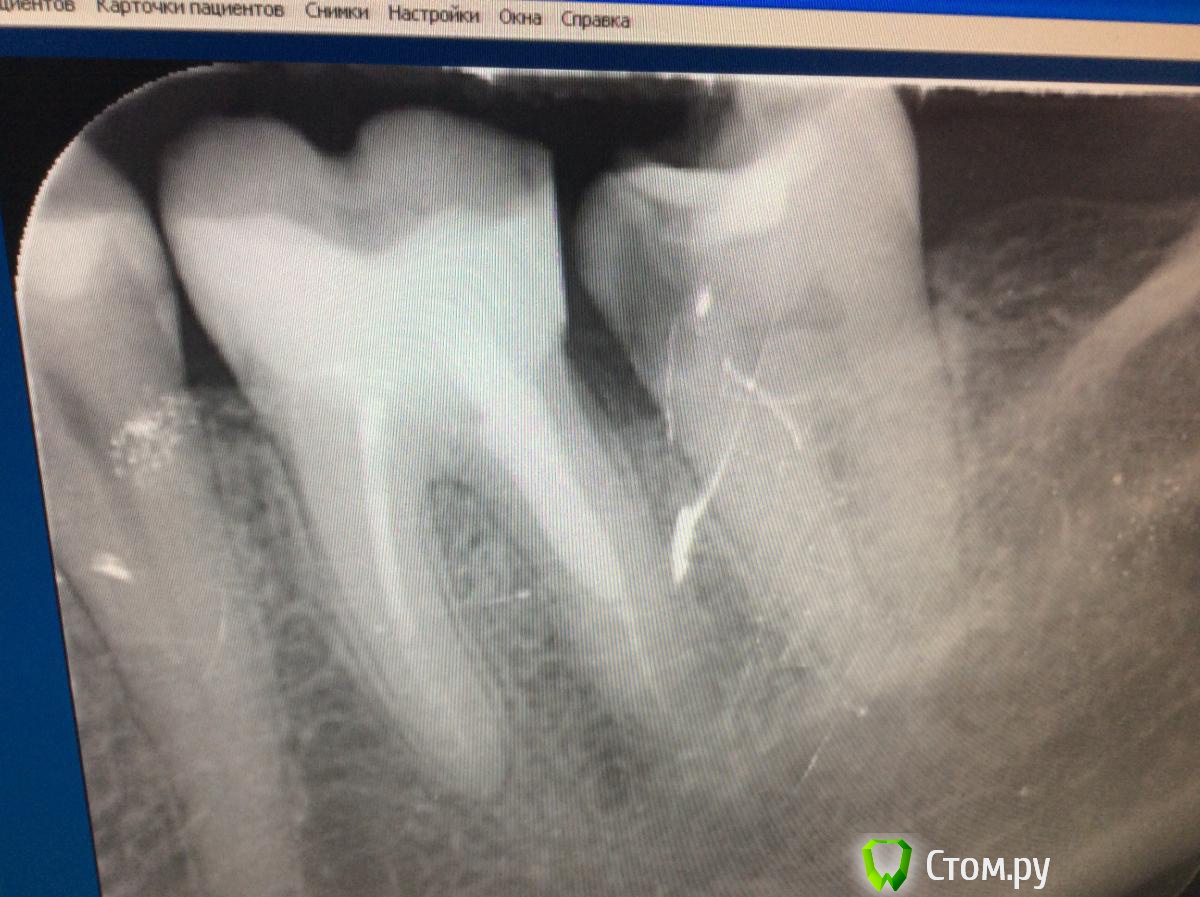

Bratok Опубликовано 14 октября, 2014 Поделиться Опубликовано 14 октября, 2014 (изменено) Всем привет! Доктора, неужели такой зуб под удаление? Феррула нет, глубтна кармана 5мм. Уступа 100% не будет на тканях зуба.. Хир удлинение + вкв+ коронка?Куда там только удлинять то? На пол корня "подкоп" ?Речь про зуб 3.7 Изменено 14 октября, 2014 пользователем Bratok Ссылка на комментарий

Л Ю С Я Опубликовано 14 октября, 2014 Поделиться Опубликовано 14 октября, 2014 Что у Вас со снимком, сплошные к..? Ссылка на комментарий

Bratok Опубликовано 14 октября, 2014 Автор Поделиться Опубликовано 14 октября, 2014 Оборудование не настроено, датчик заездили в конец. Новый нужен. Ссылка на комментарий